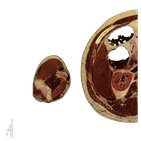

And as you can see, this can be primarily divided into two groups, which are the anterior and posterior compartments. The anterior compartment contains three muscles which are the coracobrachialis muscle, the biceps brachii and the brachialis muscles. Both the coracobrachialis and the biceps brachii muscles originate from the scapula from the inferior aspect of the coracoid process. With that in mind, let’s now look at our cross-section from the proximal portion of the arm, where we see the coracobrachialis muscle just here deep to the pectoralis major and deltoid muscles.

So, if you’ve studied the biceps brachii muscle before, you’ll know that it has two tendons or heads, and in this cross-section, we can identify both of these tendons. So, over here, we have the tendon of the short head superficial to the coracobrachialis muscle with the tendon of the long head located here between the greater and the lesser tubercles of the humerus.

So, we’re going to move distally along the arm now following these muscles as we go along, and as we work through, watch how both heads of the biceps brachii expand into the belly of the muscle with the coracobrachialis muscle tapering off at the same time before inserting into the medial aspect of the humeral shaft.

In this cross-section, we can now identify the third muscle of the anterior compartment of the arm which is located here on the anterior surface of the humerus – and this is the brachialis muscle – and as we continue on distally, we can see both bellies of the biceps brachii and the brachialis increasing in size. On the other hand, as we continue distally towards the elbow region, the biceps brachii begins to decrease in size tapering off into its tendinous parts, and from here, the tendon of the biceps will go to insert into the radius while the brachialis muscle will continue on to insert into the proximal part of the ulna.

Turning our attention now to the posterior compartment of the arm, we have two muscles to consider and they are the triceps brachii and the anconeus muscles. As the name suggests, the triceps brachii muscle has three heads which are the long head, the medial head and the lateral head. Let’s talk first about the long head.

The long head is the only head to originate from the scapula just inferior to the glenoid cavity. The other two heads both originate from the posterior aspect of the body of the humerus. Looking at our cross-sections beginning at the proximal shaft, we can see the belly of the long head of the triceps brachii here which is well-developed by this level which is we can see is pretty well-developed at this level. And if we look closely at the shaft of the humerus, we can identify the lateral and medial heads which are close to their origin points at this level.

As we continue distally along the arm, notice how the triceps brachii muscle is larger than the muscles of the anterior compartment of the arm. However, in the distal half of the arm, we can see the reverse with the triceps brachii now being smaller in comparison to the anterior muscles. When we reach the distal end of the arm, we can see the medial head of the triceps brachii as well as the tendon of the long and lateral heads more superficially. And it’s important to note at this point that the triceps brachii will continue on from here to insert onto the olecranon of the ulna.